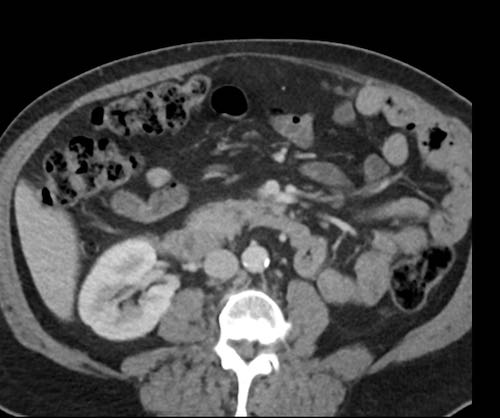

Cuộn xem ảnh CT

Ca lâm sàng 1

Cuộn qua các lát cắt.

Bạn có thể phát hiện tất cả các tổn thương cấy ghép phúc mạc không?

Bệnh nhân này đã được phẫu thuật và toàn bộ phúc mạc được ghi nhận phủ kín bởi các tổn thương u dạng kê.